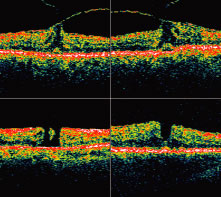

Recently, the introduction of optical coherence tomography (OCT) has allowed researchers to study the exact relationship between the vitreous and fovea in the development of macular holes. OCT is analogous to ultrasound but measures optical, rather than acoustic, reflectivity (Fig. 7). The higher frequency of light waves compared with acoustic waves allows for a much higher longitudinal resolution (10 μm vs. 150 μm).

Fig. 7. Optical coherence tomography. Vitreofoveal traction is visible in the two upper images. The two lower images show full-thickness macular holes of varying sizes. Note the subretinal fluid visible in the lower right image.

OCT evidence suggests that in most macular holes, the first step is actually the formation of a foveal pseudocyst (splitting of the retina at the fovea). It is postulated that anterior tractional forces from the prefoveal vitreous cortex cause this pseudocyst to form. The anterior wall of this cyst serves as a flap in stage 2 holes and as an operculum in stage 3 holes.15,16